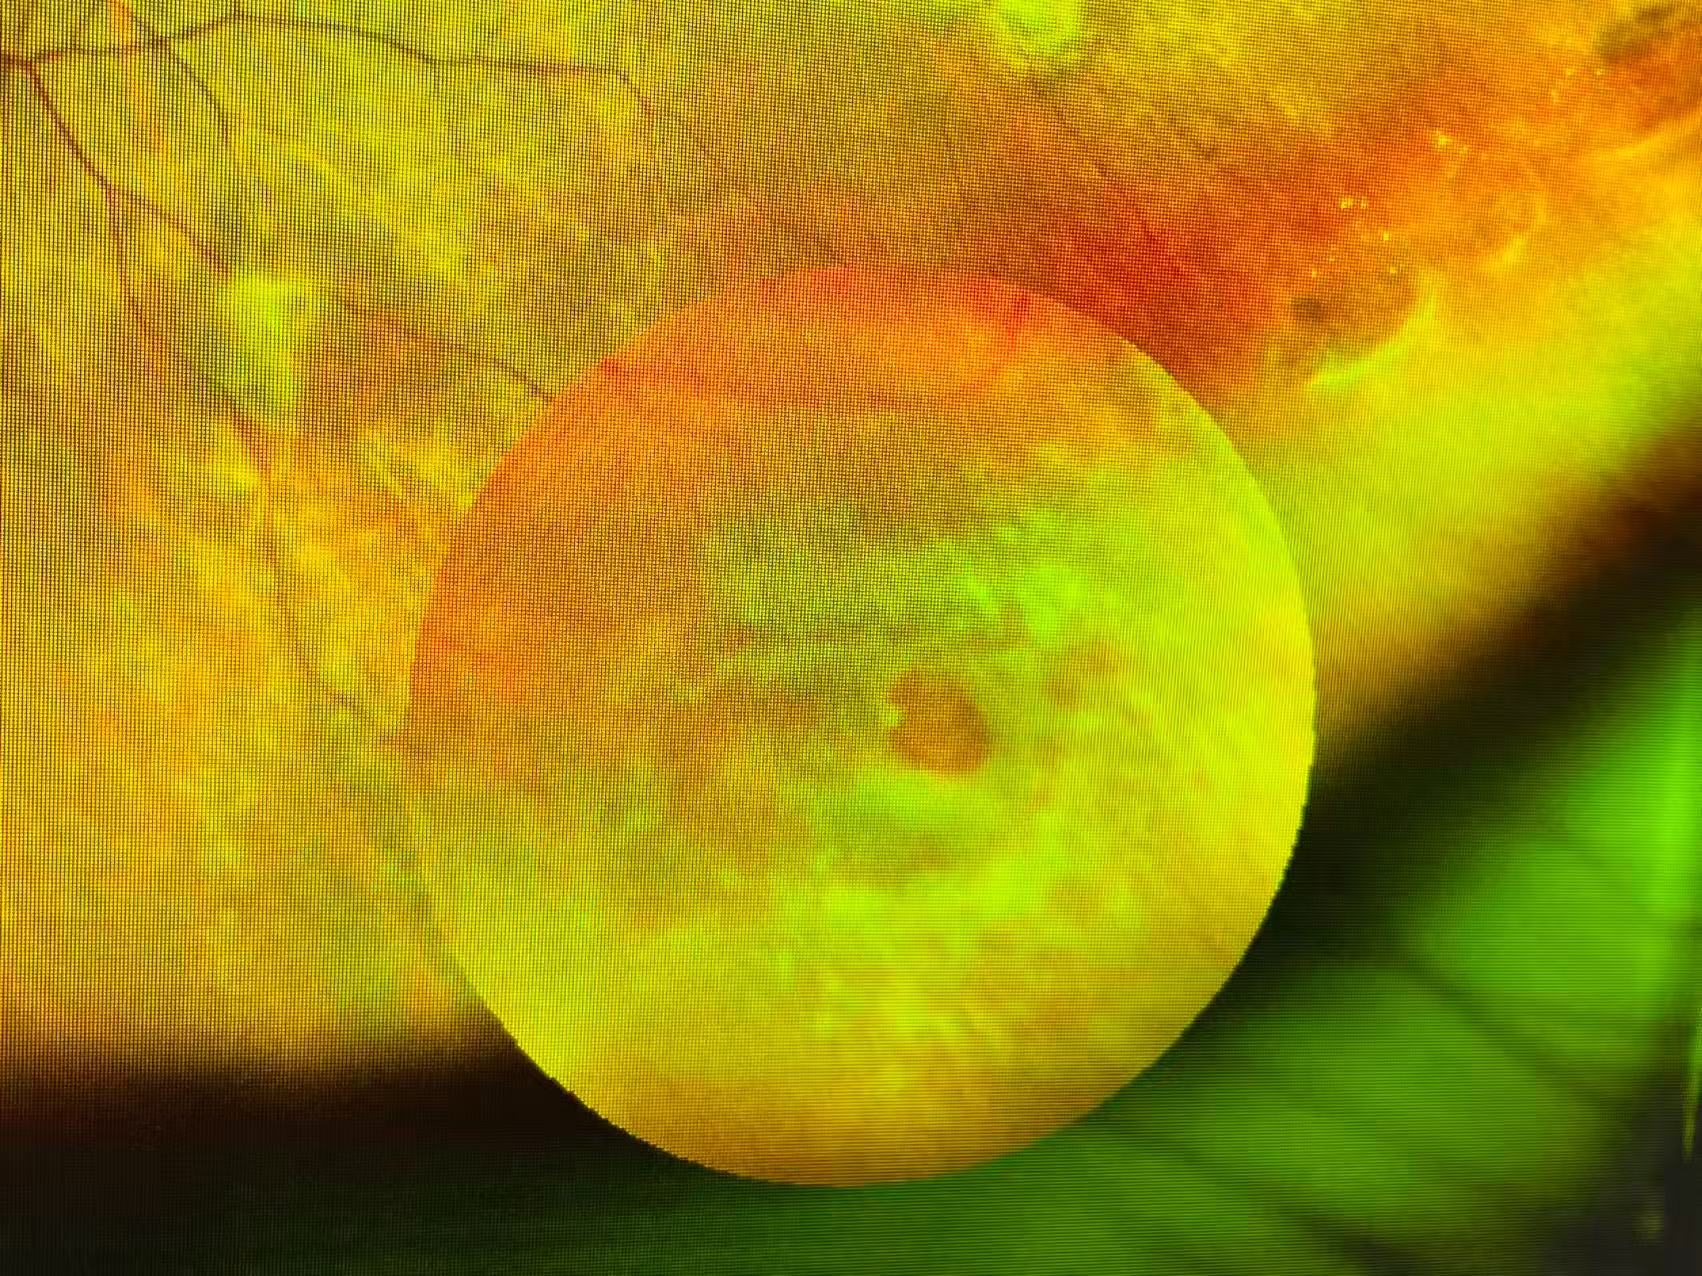

近日,医院斜弱视与小儿眼科门诊就接待了一位特殊的患者——一名准备参军摘镜的大二女生。令人意外的是,在术前常规检查中,金丽文主任发现该女生不仅眼底存在异常,还伴有内斜视症状。结合检查结果,金丽文主任第一时间给出专业建议,叮嘱其先进行眼底病变治疗及斜视针对性视觉训练,并完善颅脑MRI检查,排除头颅相关疾患,避免影响后续视力恢复及参军计划。

(患者眼底检查照片 通讯员供图)